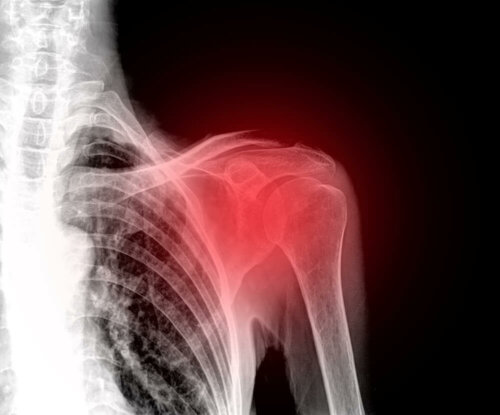

Zamrożony bark jest patologiczną dolegliwością stawu ramiennego. Schorzenie znane jest też jako zrostowe zapalenie torebki stawowej stawu ramienno-łopatkowego.

Kiedy dochodzi do zamrożenia barku, zauważa się stan zapalny maziówki, oraz zwłóknienie torebki stawowej. Badania wykazują też kolagenową tkankę, przypominają delikatną bliznę. Wszystko to prowadzi do bólu i sztywności.